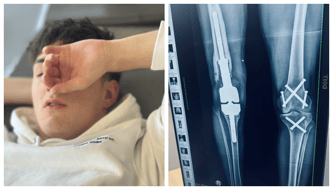

Krystian przeszedł w Stanach Zjednoczonych operację wstawienia endoprotezy restrykcyjnej. To była ogromnie skomplikowana i ryzykowna operacja. Na szczęście przebiegła zgodnie z planem. Dziś jesteśmy wdzięczni lekarzom za ich pracę i za to, że dali naszemu synowi szansę.

Endoproteza, którą obecnie ma Krystian, jest skrajnie wyrobiona.

Każdy, dosłownie każdy ruch powoduje kolejne uszkodzenia, które mogą doprowadzić do poważnego stanu zapalnego, a to oznacza jedno – zagrożenie życia.

Krystian wielokrotnie łamał kości, tracił fragmenty palców. Jego kolano i kręgosłup były stopniowo niszczone – w ciszy, bez żadnego sygnału bólu.

Dziś stoimy przed kolejnym, bardzo trudnym wyzwaniem. Endoproteza, którą Krystian ma obecnie, poluzowała się. To ogromne zagrożenie – każdy dzień grozi poważnym uszkodzeniem nogi, a nawet utratą sprawności, o którą walczyliśmy latami.